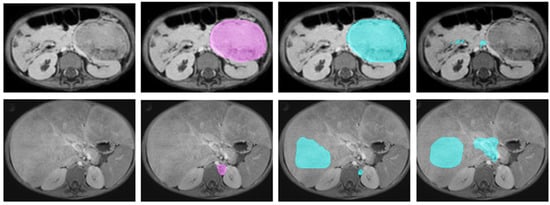

2.2.3. Manual Annotation

- Veiga-Canuto, D.; Cerdà-Alberich, L.; Sangüesa Nebot, C.; Martínez de las Heras, B.; Pötschger, U.; Gabelloni, M.; Carot Sierra, J.M.; Taschner-Mandl, S.; Düster, V.; Cañete, A.; et al. Comparative Multicentric Evaluation of Inter-Observer Variability in Manual and Automatic Segmentation of Neuroblastic Tumors in Magnetic Resonance Images. Cancers 2022, 14, 3648. [Google Scholar] [CrossRef] [PubMed]

- Veiga-Canuto, D.; Cerdà-Alberich, L.; Jiménez-Pastor, A.; Carot Sierra, J.M.; Gomis-Maya, A.; Sangüesa-Nebot, C.; Fernández-Patón, M.; Martínez de Las Heras, B.; Taschner-Mandl, S.; Düster, V.; et al. Independent Validation of a Deep Learning nnU-Net Tool for Neuroblastoma Detection and Segmentation in MR Images. Cancers 2023, 15, 1622. [Google Scholar] [CrossRef] [PubMed]